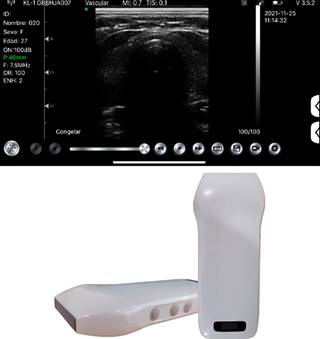

Para la correcta medición de la grasa pretraqueal: se colocó al paciente en estado consciente en posición supina con cabeza en hiperextensión (posición de olfateo), con el objetivo de exponer el cuello para su medición. Se utilizó el ultrasonido de la marca Sonowireless Plus I adaptado a un transductor lineal con frecuencias de 7.5 y 10 MHz. El ultrasonido se conectó de forma inalámbrica a un teléfono celular personal para visualizar imagen y tomar medidas con herramienta de regla incluida en la aplicación «WirelessKUS» (Figuras 1 y 2). El transductor se colocó entre la piel y membrana cricotiroidea. Para visualizar la grasa pretraqueal del paciente se evaluó la distancia comprendida entre la piel y el anillo traqueal.

Figura 3: Ultrasonido con transductor lineal de alta frecuencia en modo B, se visualiza corte transversal a nivel de cartílago traqueal identificando espesor de grasa pretraqueal de 8.78 mm.